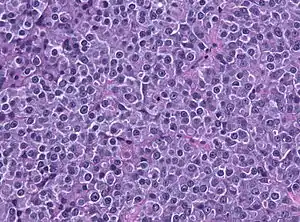

Prolactinoma é um tumor benigno glandular (adenoma) da hipófise(glândula pituitária), que produz prolactina. É o tipo de tumor mais frequente na hipófise. mais frequente em mulheres em idade fértil. Causa infertilidade e disfunção sexual em homens e mulheres.[1]